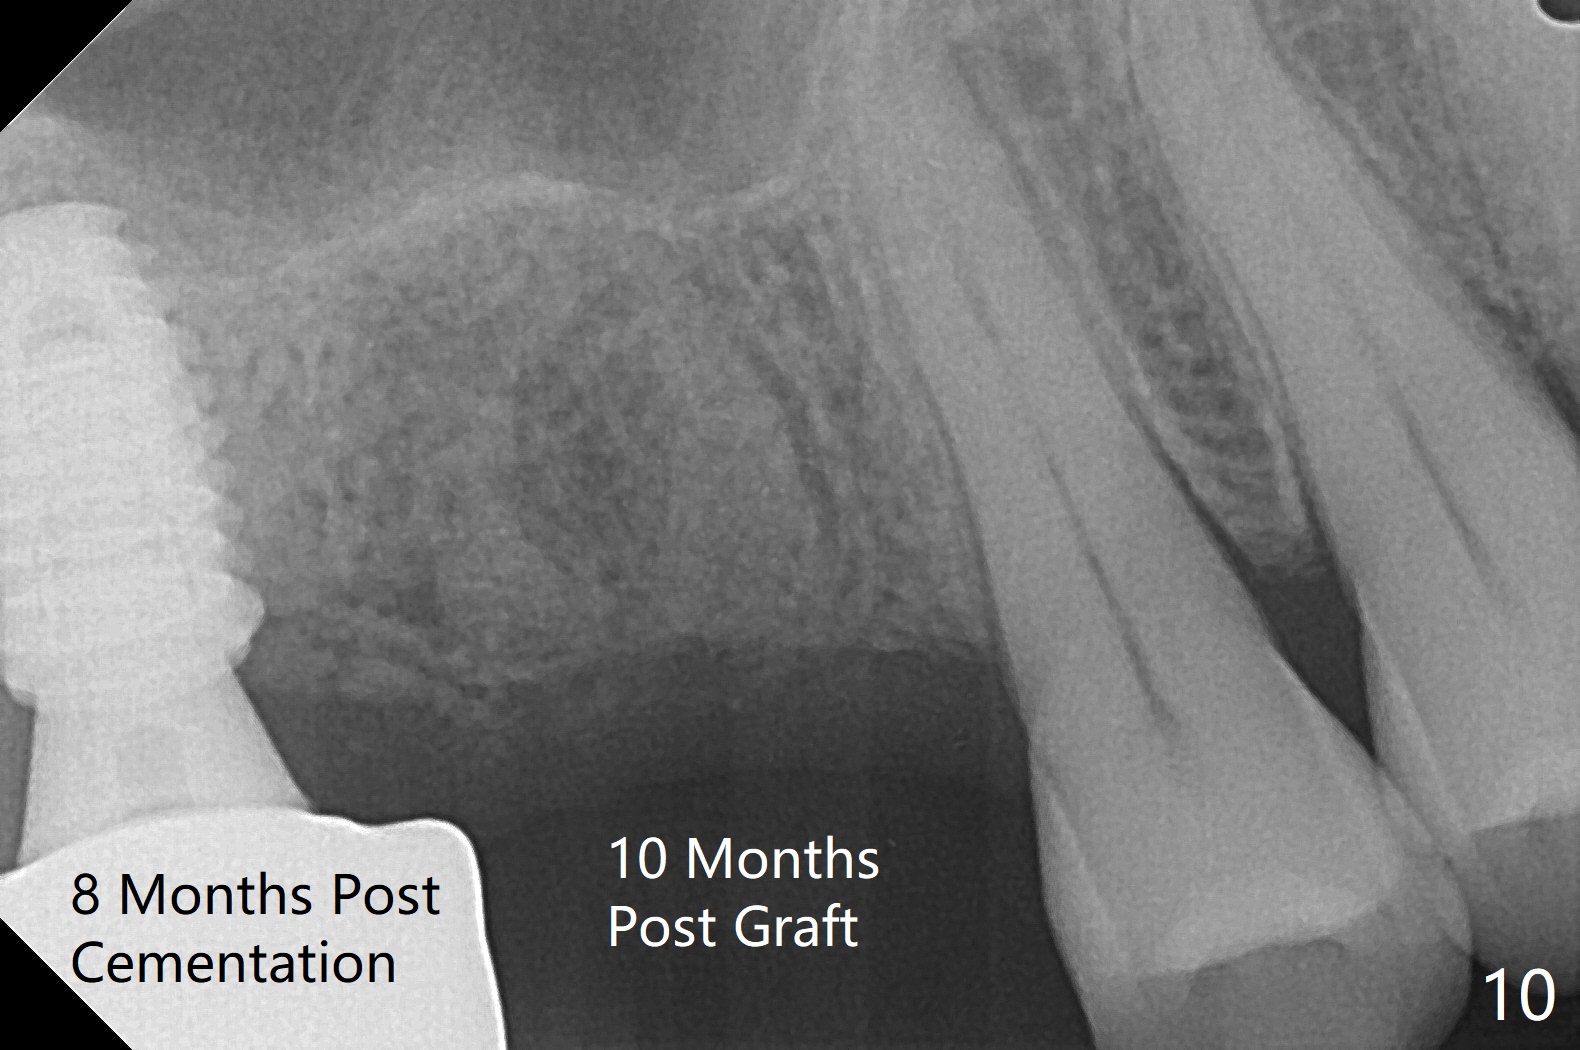

57岁男咬合力大,在右上7植体愈合中,6(3号牙)出现隐裂(图三),根管治疗后完全裂开(图四),需要拔除植骨。由于他特别害怕治疗,包括抽血,开始不想制作粘性骨块,但是考虑到我们最近用的皮质骨粉颗粒细,送到上颌磨牙牙槽窝困难,容易丢失,最后决定抽血提取上清液,制备粘性骨块(图五)。拔牙也有困难,虽然十分松动,但是无法脱位,研究两年前CT,牙根长,弯曲(图一,二),分根后才完成拔除,骨块剪成三块,分别插入三个牙槽窝(图六),覆盖PRF膜和压扁的胶原塞,缝合。术后一个月,角化龈基本保持原位。由于松弛缝合,角化龈有可能增加~6毫米(图七)。而且骨粉好像没有失去(图八,九 (P:腭侧;MB:近中颊侧;DB:远中颊侧))。术后十个月骨质高度降低(图十)。尤其是腭侧,所以植体需要偏向颊侧(图十一:B)。牙冠粘固后8个月,2号牙植体远中骨质吸收(图十二:<)。